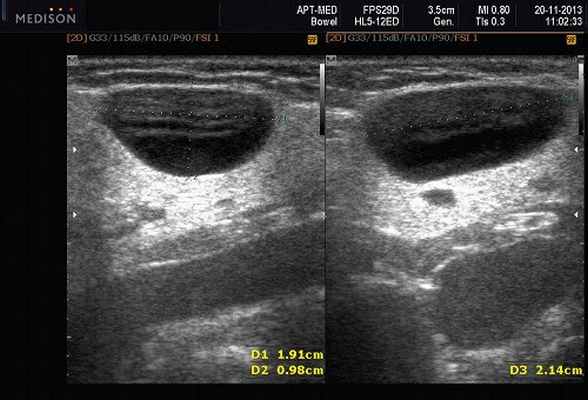

Рис. 5. Камень протока поднижнечелюстной слюнной железы.

Рис. 6. Камень в паренхиме поднижнечелюстной слюнной железы.

Рис. 7. Камень в протоке поднижнечелюстной слюнной железы.